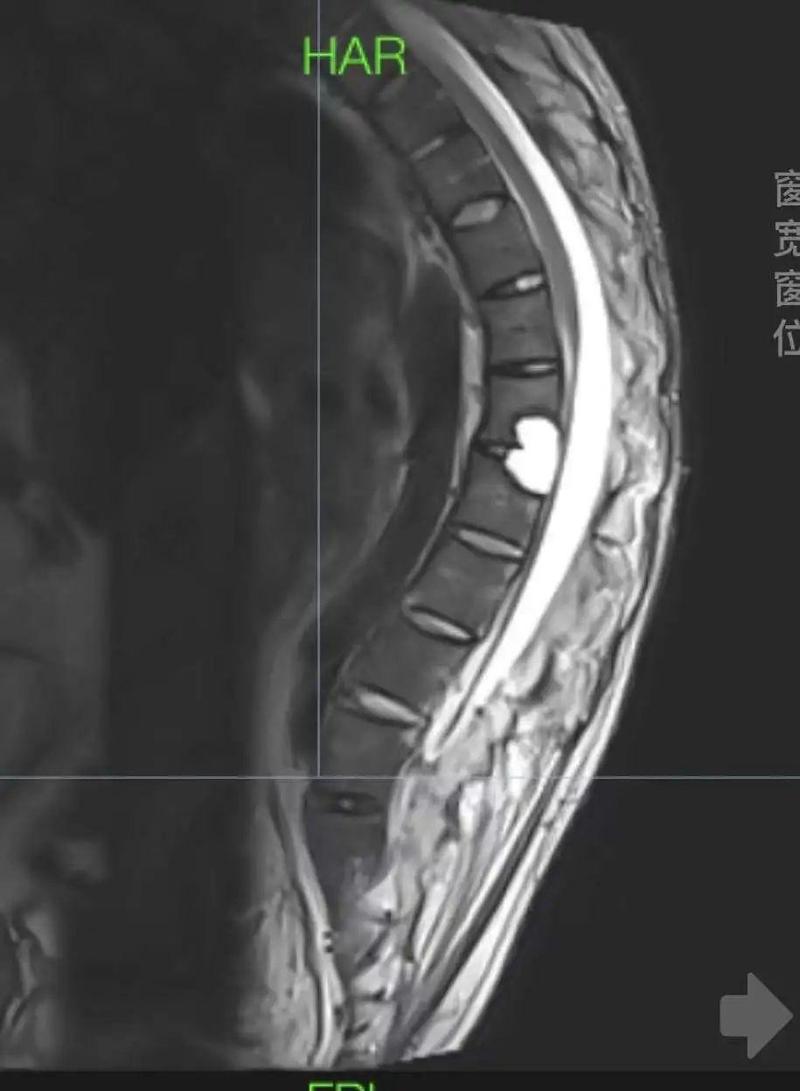

“刚住院,他就来到我的病房,拿着我之前拍的x光片仔细看着,

突然,问了周围的学生一句:你们看看这是什么?”

韦克凡顺着对方手指的方向望去,就是自己以前经常“顶压”的位置,

可他看了半天,片子上怎么看都只有一个模糊的点,“之前看过的医生,也没说过这地方有问题。”

后来,通过磁共振检查,才确认这个不起眼的点就是脊髓疝。

在已有的报道中,合并这种病症的强直患者,国内还不到10例,且多数最终选择了放弃手术。

因为一做,很有可能就是瘫痪。